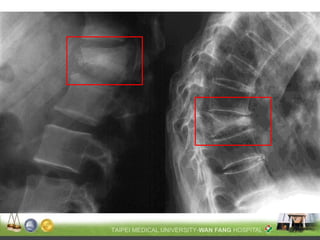

只有約25%的脊椎骨 鬆骨折會有臨床症狀

脊椎骨折常被忽略 !!

•一般X光 : 較不敏感, 需骨質流失至少30-40% 以上才可能診斷

(Grade 1)

~20-25%

(Grade 2)

~25-40%

(Grade 3)

~40%